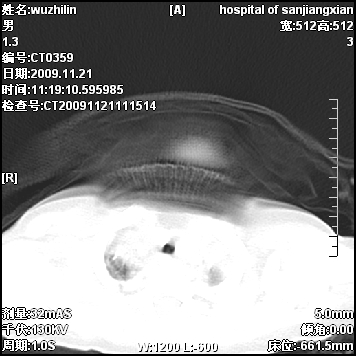

标题: PED3072: 1岁3个月患儿 胸部弥漫性病变 [打印本页]

标题: PED3072: 1岁3个月患儿 胸部弥漫性病变

弥漫性薄壁囊腔,胸膜下及肺底部占优势,双上肺磨玻璃密度影,首先考虑特发性肺间质纤维化,其次囊性肺纤维化,肺淋巴管平滑肌瘤病嗜酸性肉芽肿等;要结合临床综合考虑。

两肺布满多个薄壁含气囊腔,以下肺居多,伴磨玻璃样密度影,左侧气胸。两肺发育不全、两肺多发肺囊肿并感染,其次考虑肺囊腺瘤。